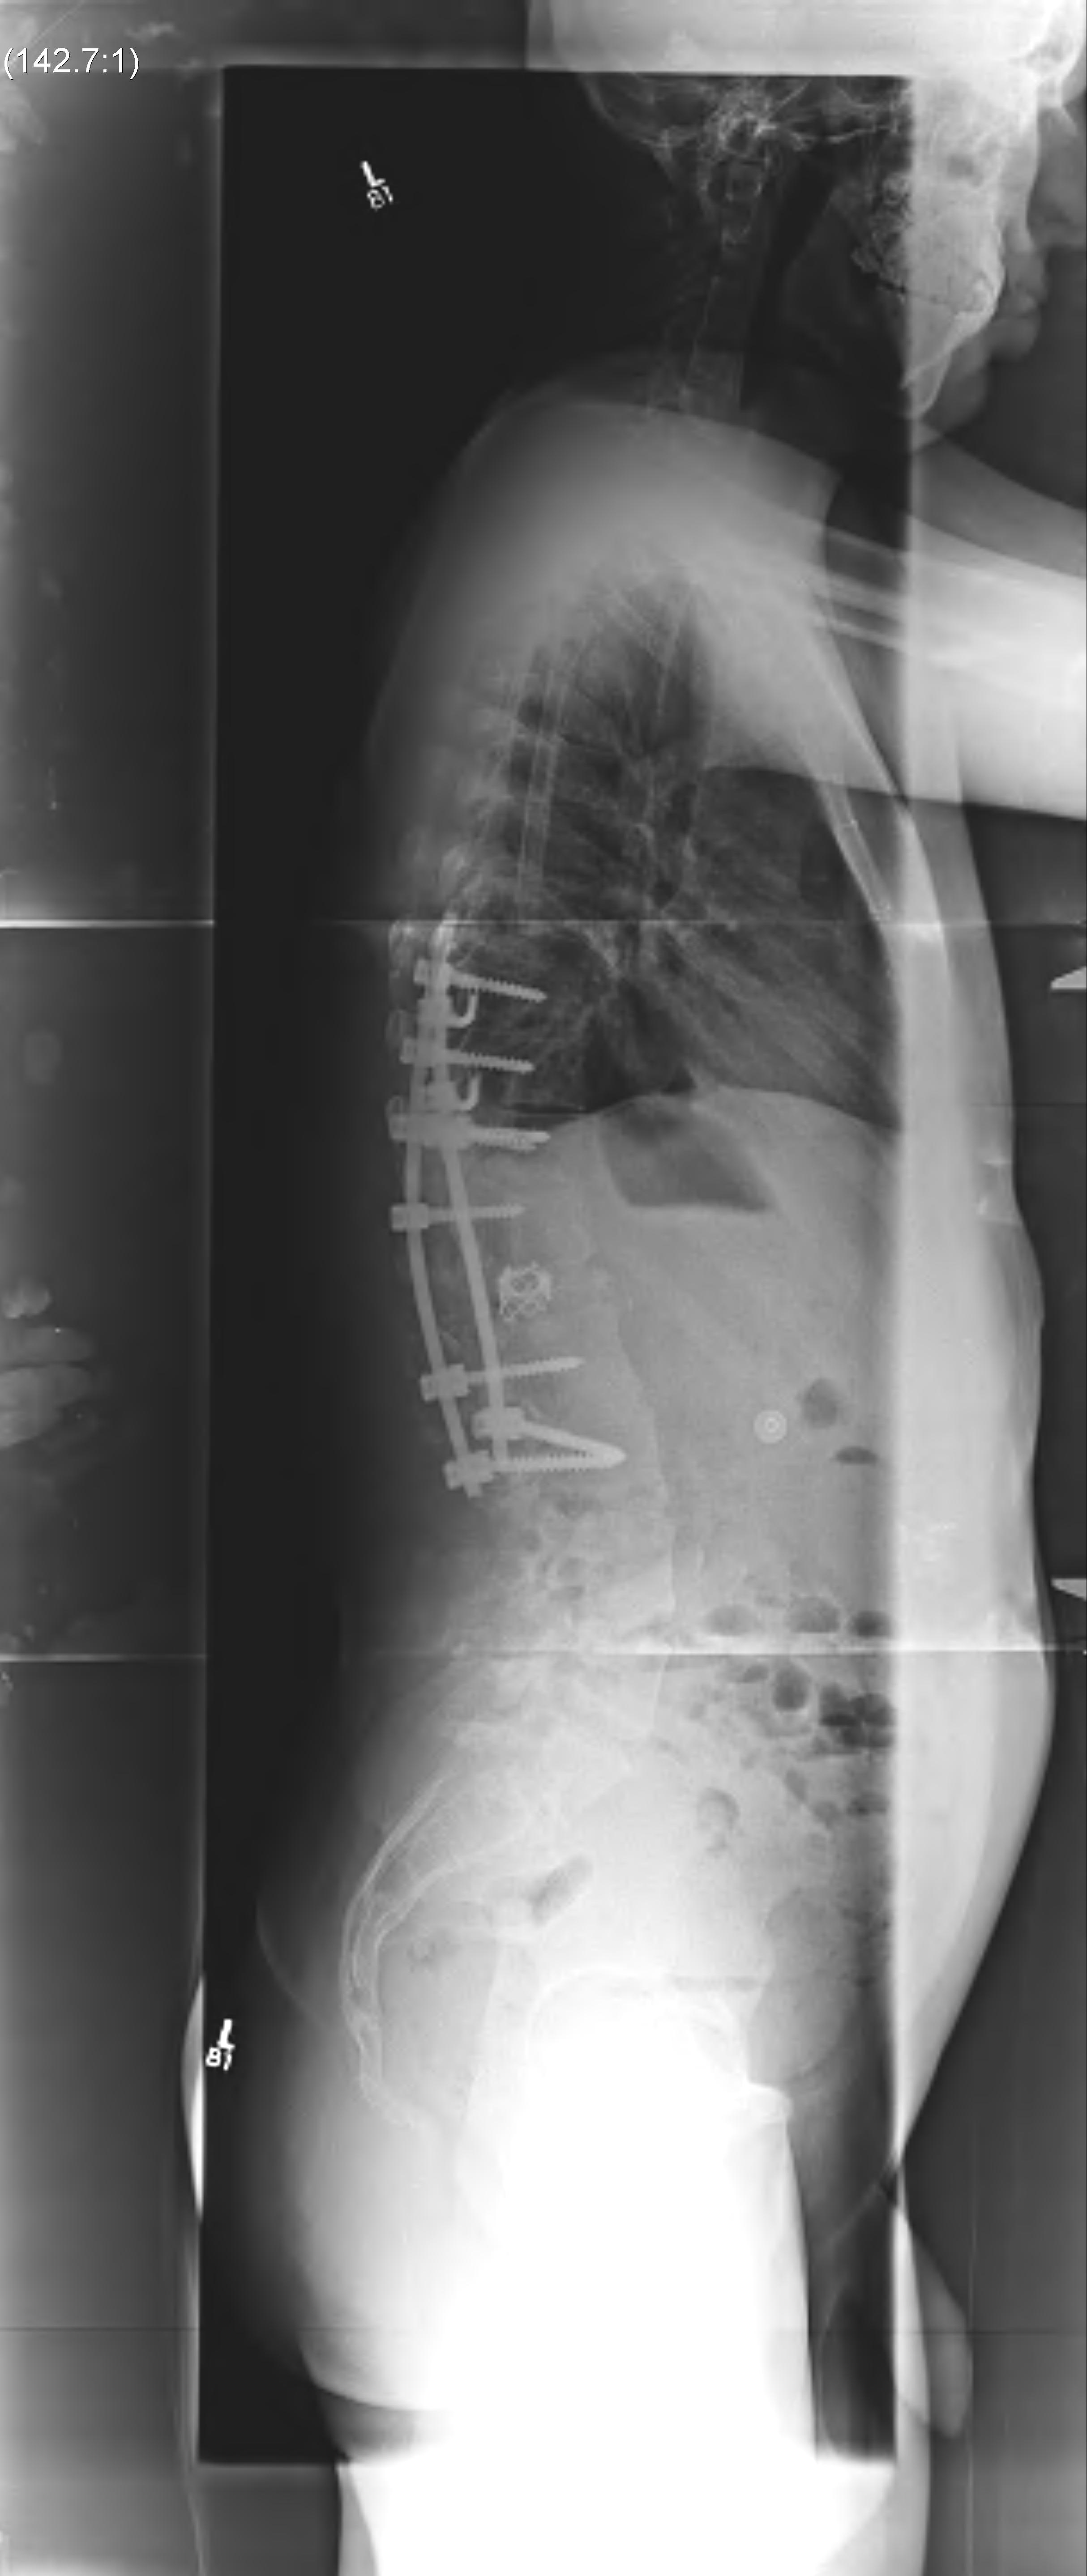

Operative

Type I

B. > 5 years and > 500

- anterior and posterior fusion

C. Neurology

- anterior decompression first